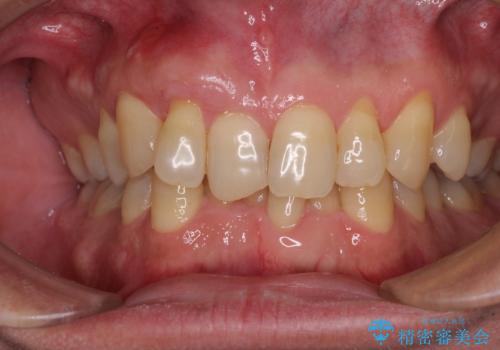

- 強い咬合力による歯肉退縮により、歯の根の黄色い色が見えてしまうことを気にされて来院された患者様です。

ディープバイトで咬合力が強く、該当歯に負担のかかりやすい咬み合わせであったため、歯肉退縮が起こりやすいと判断された患者様でした。

根面被覆を達成するとともに、歯肉の厚みを増すことで、今後歯肉退縮を起こしにくくするよう配慮した処置としました。